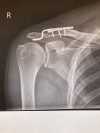

Utrhnul jsem si vazy v rameni dominantní ruky po pádu přes řidítka, původně diagnostikováno na Tossy II. – III., po kontrolním rentgenu jasná Tossy III. určenná k operaci.

- doporučuju si ofotit nebo vyžádat rentgenové snímky, já zatím fotil monitory, co mi doktoři ukázali, ale prej to dávaj i na jiná média typu CéDéčko a tak (v čem to v dnešní době přehraješ, to je už druhá otázka :-)

- pokud půjdete na operaci, nedoufejte v nějakou laparoskopii, je potřeba pečlivě prozkoumat co a kde se utrhnulo, na rentgenu to nidko přesně nepozná a vidět jsou jen kosti jak nejsou tam, kde mají být (ostatně jizvy z „boje“ prej chlapa ctí)